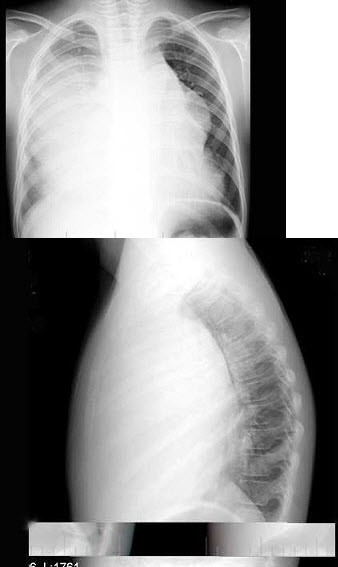

32、单项选择题

男,65岁,胸痛,胸片检查如图,下列诊断中最可能的是()

A.右肺胸膜肥厚

B.右肺不张

C.右侧胸腔积液

D.右肺炎症

E.以上都不对